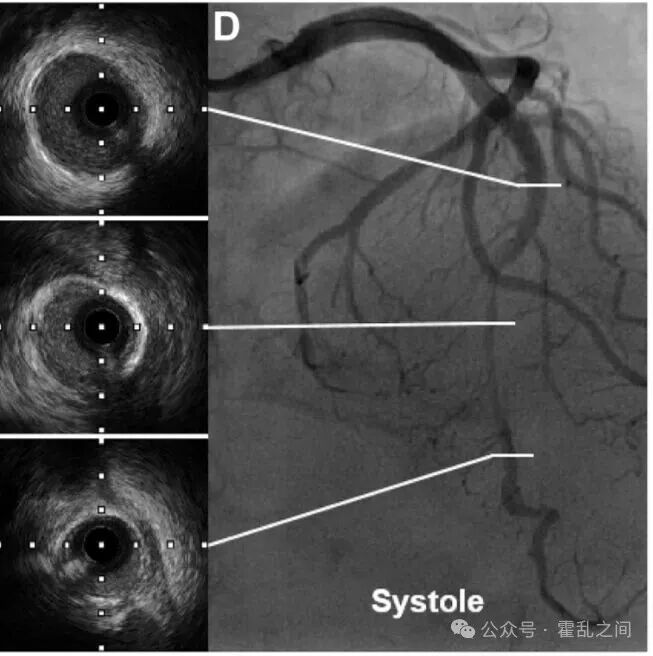

图:收缩期前降支的典型冠脉造影及对应IVUS图像(“挤奶现象”的节段存在“半月现象”)